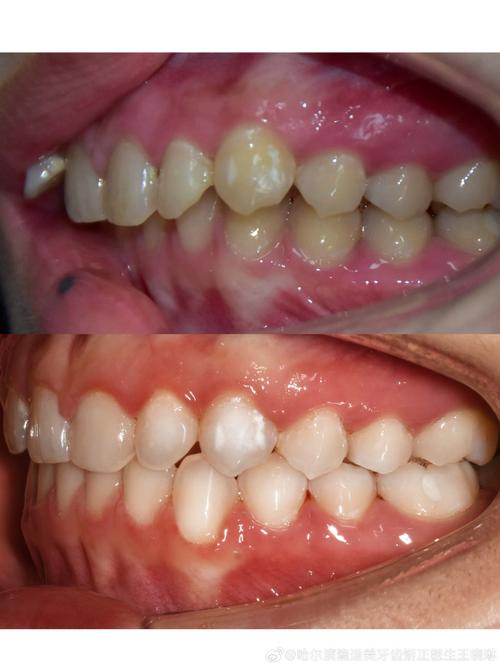

适应症:主要用于纠正II类错颌畸形,如上颌前突、上颌磨牙近中关系(深覆盖、深覆颌),通过将上颌磨牙或下颌磨牙向远中移动,改善上下颌磨牙的咬合关系,为前牙内收创造空间。

磨牙近中移动

适应症:主要用于III类错颌畸形,如下颌磨牙远中关系、下颌前突,通过将下颌磨牙向近中移动,或上颌磨牙向近中移动(需谨慎,避免前牙反颌加重),改善磨牙关系。